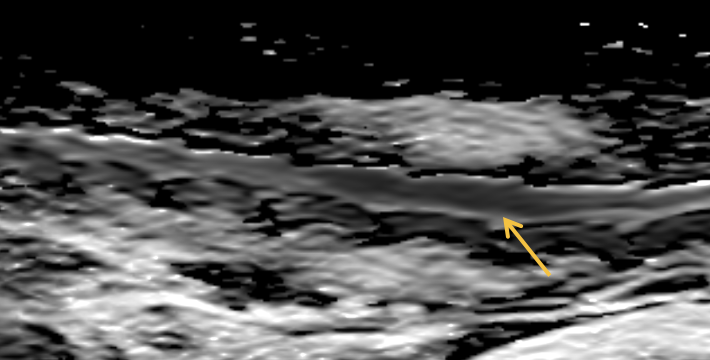

향상된 확산강조영상(Diffusion weighted imaging) 을 이용한 미세 뇌 손상 정밀 평가

확산강조영상에도 AI 기술이 적용되어 이전보다 향상된 확산강조영상을 제공합니다.

이전에 확인하기 어려웠던 척수 실질에 대한 확산강조영상 정밀 평가 및 미세 뇌 실질 병변을 정밀하게 평가합니다.

뇌 실질 내 2mm이내의 미세 뇌출혈 (microbleeding) 병변

척수 실질 경색성 변화

DWI(상)/ ADC(하)